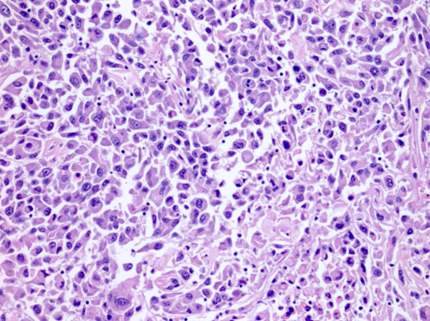

Thường gặp các đám và bè tế bào sắp xếp chặt chẽ, tế bào có bào tương sáng và màng tế bào rõ. Bào tương hạt bắt màu eosin có thể được quan sát trong các khối u độ mô học cao hoặc ở vùng lân cận các ổ xuất huyết hay hoại tử. Hệ thống các mạch máu nhỏ, thành mỏng, phân nhánh dạng cây là một đặc điểm chẩn đoán quan trọng, đặc biệt trong các trường hợp có bào tương hạt eosin. Các kiểu cấu trúc kiến trúc gồm dạng đặc, dạng phế nang hay dạng ổ (alveolar hoặc nested), dạng tuyến nang hay ống (acinar hoặc tubular), dạng vi nang chứa hồng cầu thoát mạch hoặc dịch ái toan, và đôi khi dạng đại nang. Có thể gặp cấu trúc nhú khu trú, tuy nhiên sự hình thành nhú nổi bật làm tăng khả năng các phân nhóm khác như u thận tế bào sáng dạng nhú, ung thư biểu mô tế bào thận có tái sắp xếp TFE3, biến đổi TFEB hoặc đột biến ELOC. Mô đệm thường không đặc hiệu, không có phản ứng xơ sinh, trái ngược với ung thư biểu mô ống góp hoặc ung thư biểu mô niệu mạc, và chỉ có đáp ứng viêm tối thiểu. Các đặc điểm độ mô học cao bao gồm biệt hóa dạng rhabdoid với các tế bào ác tính lớn, độ ác tính cao, bào tương eosin đồng nhất phong phú, nhân lệch tâm và các thể vùi eosin hình cầu trong bào tương, cũng như biệt hóa dạng sarcomatoid, có thể xảy ra ở bất kỳ phân nhóm ung thư biểu mô tế bào thận nào. Hoại tử khối u là một đặc điểm có thể gặp. Các biến thể mô học ít gặp, hiện chưa rõ ý nghĩa tiên lượng, bao gồm dạng nang, dạng giả nhú, tạo xương lạc chỗ, các thể cầu hyaline trong và ngoài tế bào, các thể vùi bào tương bắt màu kiềm, sự hiện diện phong phú của tế bào khổng lồ đa nhân, các u hạt dạng sarcoid hoặc hình ảnh myospherulosis. Ung thư biểu mô tế bào thận tế bào sáng có đột biến BAP1 thường biểu hiện cấu trúc nhú, bào tương eosin và các thể cầu trong bào tương. Trên thực hành, các vùng u độ mô học thấp hơn với hình thái điển hình của ung thư biểu mô tế bào thận tế bào sáng là những vùng hữu ích nhất cho chẩn đoán, trong khi các khối u độ mô học cao hơn có thể biểu hiện các đặc điểm chồng lấp với các тип ung thư biểu mô tế bào thận khác.

Hình 5. ccRCC với hệ thống mạch xoang dạng cây phân nhánh, thành mạch mỏng